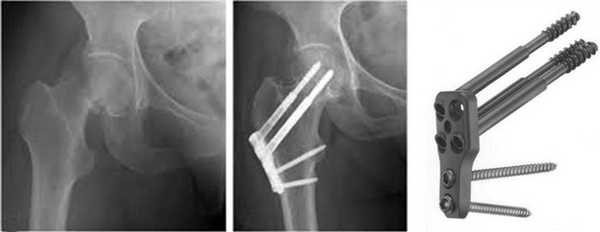

Улучшенный вариант бедренного штифта - проксимальный бедренный штифт PFNA от компании Титанмед

В случае, когда перелом бедра сочетает в себе повреждение как диафиза, так и проксимального отдела кости, операцией выбора является установка проксимального бедренного штифта PFNA.

Тонкость и уникальность такой конструкции обусловлена тем, что по сравнению с классическими вариантами гамма-стержня, протез PFNA имеет большую длину основного штифта, но при этом сохраняет структуру с одним шеечным винтом без использования второго дублирующего. Это придает импланту дополнительную антиротационную стабильность.

Исследованиями установлено, что антиротационные бедренные штифты PFNA отличаются гораздо более равномерным распределением нагрузки между отломками костей по сравнению с обычными аналогами.